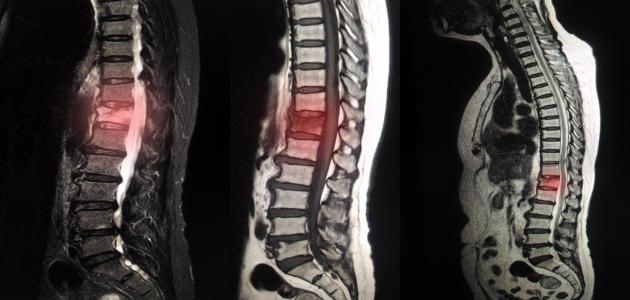

يتضمن إجراء الرنين المغناطيسي للظهر استخدام مجال مغناطيسيّ وضرباتٍ من طاقة الموجات الراديوية بهدف التقاط صورٍ للعمود الفقري، وتجدر الإشارة إلى أنّ هذا النّوع من التصوير قادر على منح معلوماتٍ مُختلفة والكشف عن مشاكل لا يُمكن رؤيتها عند إجراء اختبارات التصوير الأخرى؛ كالتصوير بالأشعة السينيّة، أو الموجات فوق الصوتيّة، أو التصوير المقطعي المحوسب، ويتضمن إجراء الرنين المغناطيسي وضع الجسم داخل آلةٍ تحتوي على مغناطيس قويّ بما يُمكّن من حفظ الصّور الناتجة عن هذا الإجراء وتخزينها في جهاز الحاسوب، وتجدر الإشارة إلى احتماليّة استخدام مادة تبايُن أثناء التّصوير بالرنين المغناطيسي بهدف إظهار أجزاءٍ مُعينة من الجسم بشكلٍ أوضح.[١]

يُجرى تصوير الظهر بالرنين المغناطيسي لعدّة أهداف، وفيما يأتي بيان لأبرزها:[٢]

- تقييم تشريح العمود الفقري ومُحاذاته.

- الكشف عن الاضطرابات الخلقيّة غير الطبيعيّة في الفقرات أو الحبل الشوكي.

- الكشف عن إصابة العظام، أو الأقراص، أو الأربطة، أو الحبل الشوكي بعد تعرّض العمود الفقري لصدمة أو ضربة مُعينة.

- تقييم أمراض الأقراص الغضروفيّة (بالإنجليزيّة: Intervertebral Disks) وأمراض المفاصل الفقريّة.

- البحث حول الأسباب المُحتملة للشعور بآلام الظهر.

- تقييم مدى انضغاط الحبل الشوكي والأعصاب أو التهابها.

- تقييم مدى تأثير العدوى في العمود الفقري، والأقراص، ومحتويات العمود الفقري؛ بما في ذلك الحبل الشوكي وأغشيته.

- تقييم الأورام الناشئة أو المُنتشرة في الفقرات، أو الحبل الشوكي، أو الأعصاب، أو الأنسجة الرخوة المُحيطة.

- المُساهمة في التخطيط للعمليات الجراحيّة المُراد إجراؤها في العمود الفقري.

- مراقبة التغيّرات التي تطرأ على العمود الفقري بعد الخضوع لعمليّةٍ جراحيّة؛ مثل تشكّل النّدوب أو حدوث العدوى.